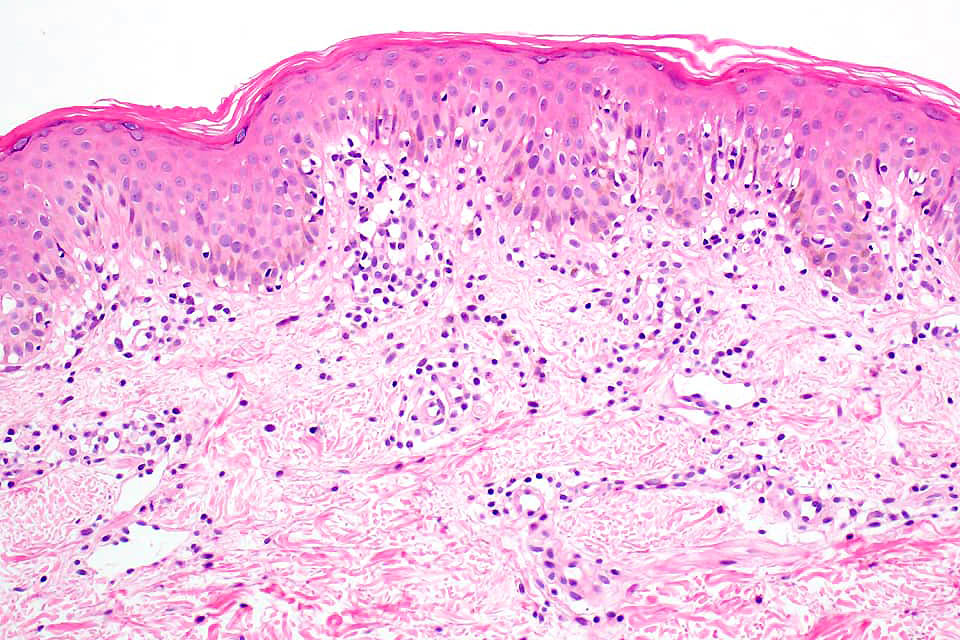

Histological features

•Indistinguishable from classical mycosis fungoides with the additional feature of marked pigmentary incontinence

•CD8+ve cells may predominate

•Histology is identical to classical mycosis fungoides